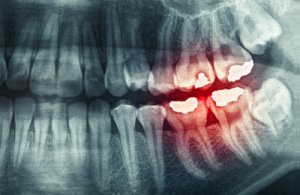

- Voortijdige erosie of afslijten van het glazuur van de tanden. Stukken tandglazuur en vullingen kunnen afbreken. De tanden gaan abnormaal snel afslijten.

- Breuken in de tanden of het los komen te zitten van de tanden.

- Extreme overgevoeligheid van de tanden.